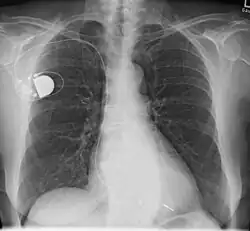

Herzschrittmacher

Ein Herzschrittmacher (HSM) oder Pacemaker (PM) (englisch für ‚Schrittmacher‘) ist ein elektronischer Impulsgenerator zur (meist regelmäßigen) elektrischen Stimulation (Anregung) des Herzmuskels zur Kontraktion. Das Gerät dient der Behandlung von Patienten mit zu langsamen Herzschlägen (bradykarde Rhythmusstörungen).

- Intrakardiale Stimulation durch Implantat: Der Herzschrittmacher wird oberhalb der rechten oder linken Brust unterhalb des Schlüsselbeines zumeist unter die Haut (subkutan) oder bei hageren Patienten unter den großen Brustmuskel (submuskulär) implantiert. Die Elektroden werden transvenös zum rechten Vorhof oder rechten Ventrikel geführt (beim biventrikulären Schrittmacher wird eine dritte Elektrode über den rechten Vorhof und den Koronarvenensinus zur Posterolateralwand des linken Ventrikels vorgeschoben). Diese Art der Implantation eines Herzschrittmachers ist die in der Praxis am häufigsten angewendete.